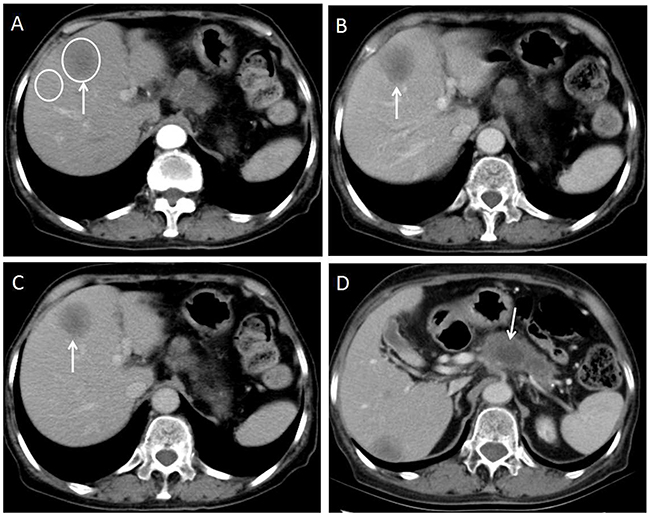

Figure 4: 70-year-old woman with moderately-poorly differentiated pancreatic adenocarcinoma. (A) Axial CT image on the hepatic arterial phase shows a hypo enhanced liver metastasis in the left lobe of the liver(arrow). Two oval shaped ROIs were placed on the largest lesion and adjacent normal liver. The metastasis-to-liver ratios on hepatic artery phase and portal venous phase were 70.7% and 60.2% respectively. (B and C) Axial CT image on the portal venous phase and equilibrium phase show the lesion keeps hypo enhancement that meets the plateau enhancement pattern(arrows). (D) Axial CT image on the portal venous phase shows hypo enhanced primary tumor in the pancreas(arrow).